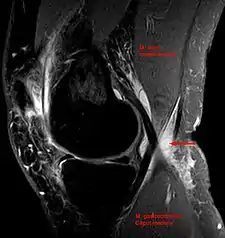

Baker's cyst on axial MRI with communicating channel between the semimembranosus muscle and the medial head of the gastrocnemius muscle.